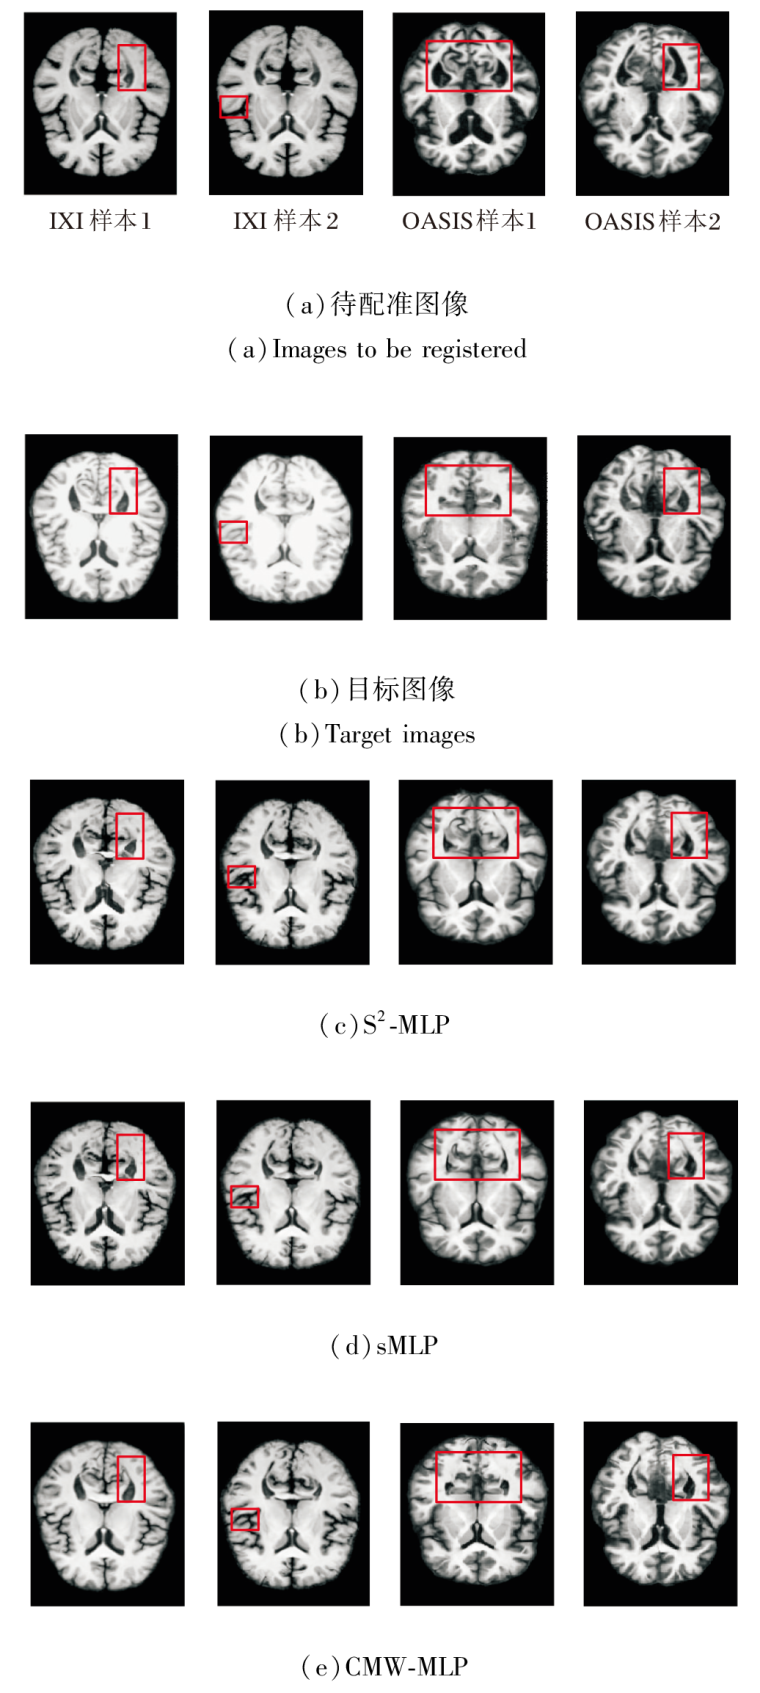

CMW-MLP作为PyraMLP-Net的核心组件, 通过计算输入特征间的局部相关性以捕获多范围依赖关系.为了验证其必要性, 以PyraMLP-Net为基准, 将CMW-MLP分别替换为S2-MLP(Spatial-Shift MLP)[25]和sMLP(Sparse MLP)[26]进行对比.

同样在IXI、OASIS数据集上各选取2个样本, 各模块的图像配准结果如图13所示, 对PyraMLP-Net性能的影响如图14所示.由图可看出, CMW-MLP在IXI、OASIS数据集上的配准精度均显著高于S2-MLP和sMLP.这一优势主要源于其两项核心设计.

1)三维相关层显式建立局部特征的空间对应关系, 提供像素级对齐的强引导信号.

2)多窗口并行架构能同时捕捉不同尺度的空间依赖.相比之下, S2-MLP和sMLP仅能进行全局、无差别的特征混合, 缺乏对局部结构关联的显式建模和对多尺度形变的针对性处理, 因此难以精准捕捉解剖细节的对应关系.